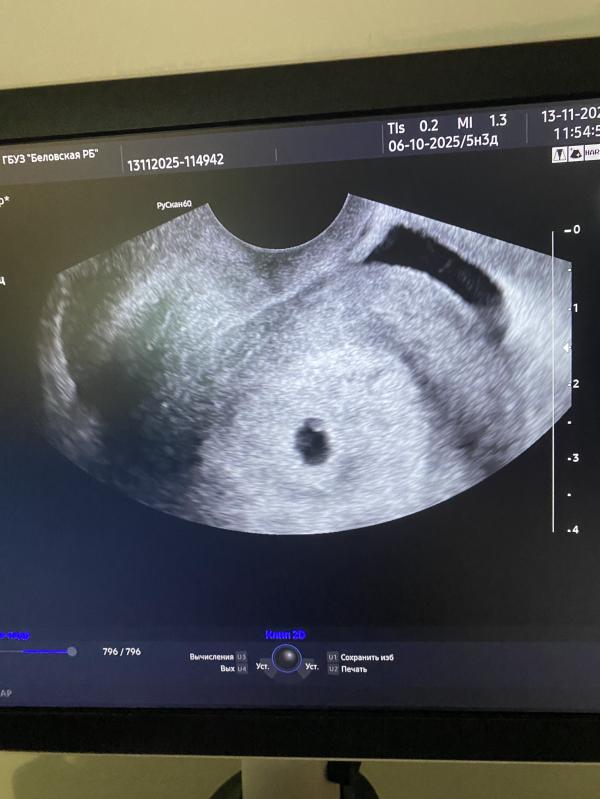

Первое УЗИ при беременности: размеры плодного яйца

post image

Крошка наша🥹🥰

Плодное яйцо 9мм

Желточный мешочек 2,5мм

13.11.2025